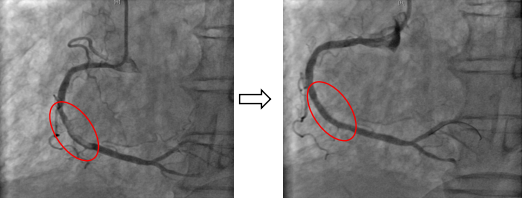

急诊冠状动脉介入术中,手术团队迅速锁定患者右冠脉内大量血栓,为患者进行了冠状动脉内血栓抽吸术、冠状动脉内球囊扩张术,并顺利植入1枚最新一代药物洗脱支架。术后患者的胸痛症状立即缓解,收入心脏内科重症监护室进行后续治疗。